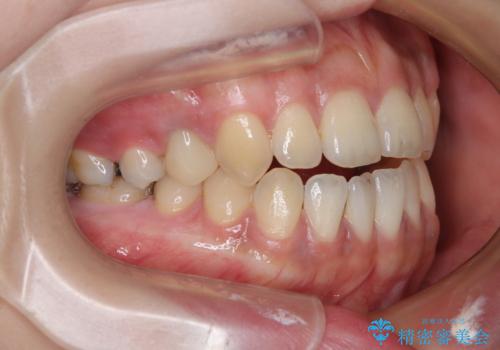

開咬をワイヤー装置で矯正治療

- 上下前歯が非接触となっている咬み合わせを気にして来院された患者様です。

開咬となっている原因の大半は、舌の突出癖によるものであるため、治療開始前から舌のトレーニングを開始し、スムーズに治療が進むようにしました。

開咬の方は、インビザライン矯正治療が適していますが、自己管理の煩わしさと、転勤の可能性がありマウスピース矯正であると通院しなくなるだろうとのことで、ワイヤー装置にて矯正治療を行うこととしました。